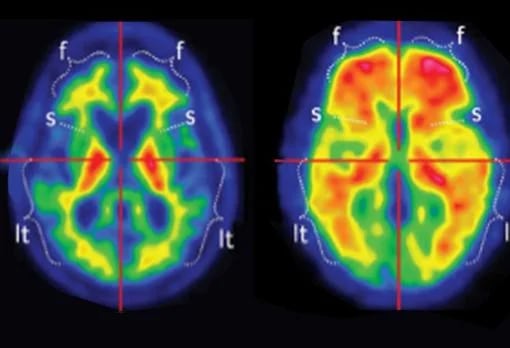

Con el avance de las técnicas de imágenes cerebrales, los investigadores ahora pueden observar cómo estas afecciones se manifiestan en cerebros vivos y los patrones comienzan a mostrar similitudes inesperadas.

Durante años, tanto en el estudio del autismo como en el del Alzheimer, la investigación se concentró en regiones cerebrales aisladas: qué áreas eran más grandes o más pequeñas, más o menos activas. Por ejemplo, a los científicos les llamó la atención que el Alzheimer estuviera asociado con la contracción de una región conocida como la amígdala, vinculada con la emoción, el miedo y el procesamiento social. En el autismo, en cambio, la amígdala suele aparecer agrandada, aunque los resultados han variado según la edad de las personas estudiadas y el diseño de los trabajos.

Cada vez más, sin embargo, el foco se desplazó de las regiones individuales a las conexiones entre ellas: las redes que permiten que el cerebro funcione como un conjunto integrado.

En dos campos que durante mucho tiempo avanzaron por separado, los investigadores convergieron, en los hechos, en una misma idea.

En el autismo, los hallazgos presentados el año pasado en la conferencia anual de la Asociación Neuropsiquiátrica Estadounidense sugieren que la densidad y la fortaleza de las conexiones sinápticas pueden correlacionarse con el nivel de funcionamiento. En algunos casos, una conectividad más sólida se asocia con un mejor desempeño en la vida cotidiana. En el Alzheimer, en cambio, la pérdida de esas mismas conexiones se correlaciona de manera muy estrecha con el deterioro cognitivo, y algunos especialistas consideran que puede tratarse de un indicador anatómico más preciso que la acumulación de placas amiloides o de los ovillos formados por la proteína tau, durante mucho tiempo considerados los rasgos definitorios de la enfermedad.